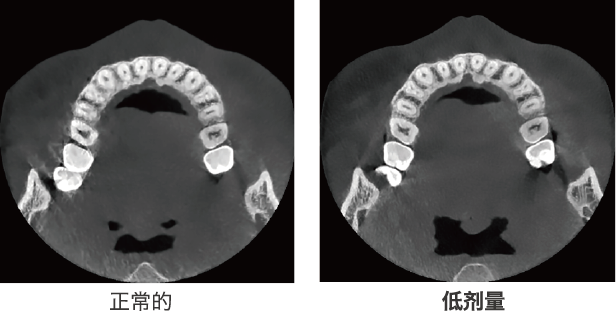

低劑量,高質(zhì)量

通過先進(jìn)的工程學(xué)技術(shù),低劑量的X射線也可以獲得高質(zhì)量的圖像。

降噪技術(shù):bright CT無噪點(diǎn)圖像,不會(huì)丟失有價(jià)值的細(xì)節(jié),并允許低劑量模式通過降低噪點(diǎn)來獲得影像。此功能在使用小體素模式(例如在牙髓成像模式下)。